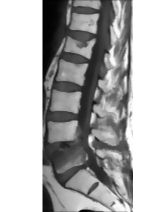

Sagittal T1 MRI of the Lumbosacral Region Showing an L4-L5 Herniated Disk